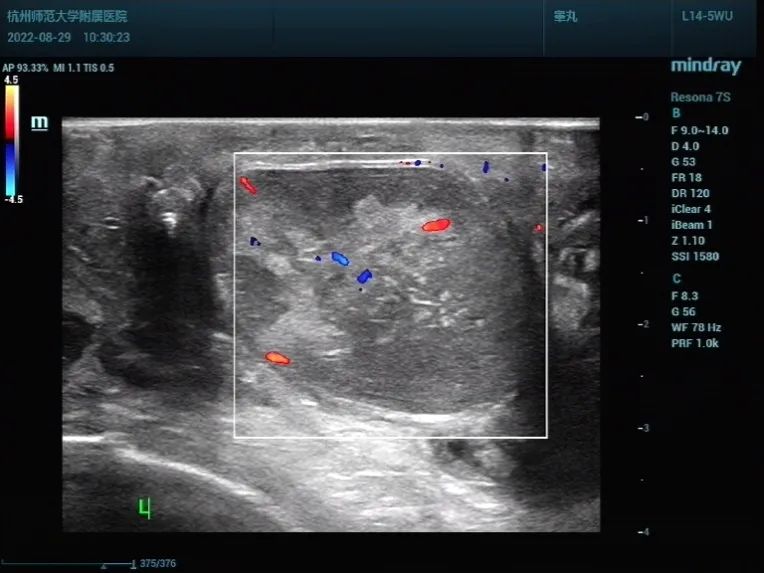

左侧睾丸大小约 3.4×2.7 cm ,左侧睾丸长轴呈横位,内回声杂乱不均(图 1 ),CDFI 示睾丸内未见血流信号(图 2 、图 3 ),左侧精索走形异常,CDFI:见呈漩涡状的血流信号(图 4 )。

图 3 CDFI: 左侧睾丸内未见血流信号(左侧睾丸矢状切面)

图片:作者提供